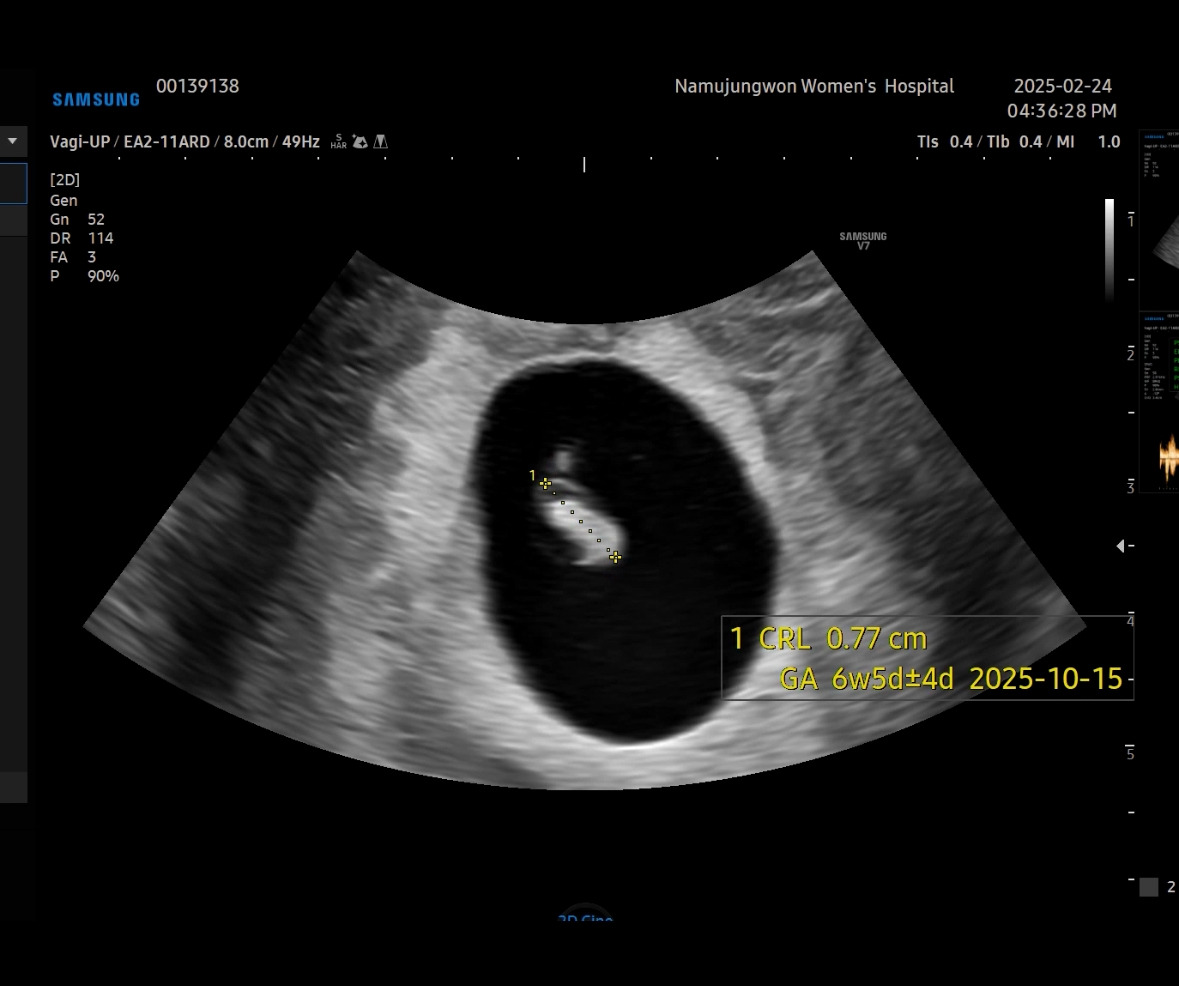

병원을 비교해보고 싶기도 하고 해서 집에서 더 가까운 산부인과로 그다음 주에 방문했다. 난황 말고 아기가 된 모습을 기대하며.. 6주 차 5일에 만난 꼬물이!

머리부터 꼬리까지의 길이가 0.77cm로 6주 차 5 일이라고 이날 확정되었다. 그래서 출산 예정일은 25년 10월 15일! 아직은 출산의 무서움보다는 그날이 너무너무 기다려진다.

머리 쪽에 투명 공간에는 앞으로 뇌가 만들어지는 부분이고 아래에 꼬리는 점점 사라질 거라고 했다. 그리고 머리에 붙어있는 동그라미가 작아지고 있는 난황이다.

지금은 자궁이 꼬물이에 비해 넉넉해 보였다.

심장소리를 잡고 엄청 볼륨을 높여 주셔서 순간 울컥하는 마음에 눈물이 고였다. 신기하다. 1센티가 안 되는 저 꼬물이가 심장이 뛰고 있다는 게.